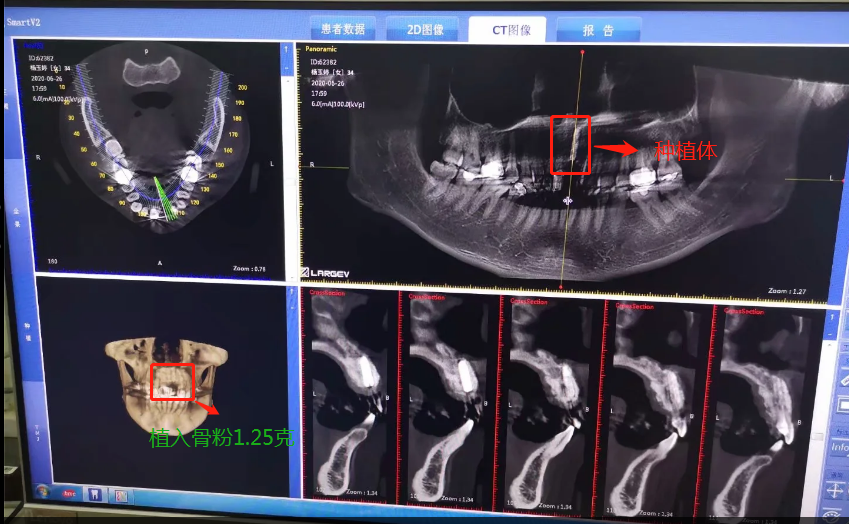

植入種植體后拍的CT

2020年6月26日,終于等到了,我要種植了牙根啦,我牙根弄了法國安卓建品牌的種植體,之前還去幾家口腔門診和烈士陵園的光華口腔也咨詢過和對比價(jià)格,瑞士ITI品牌太貴了(還有別的品牌M美國皓圣、韓國登騰、德國ICX、瑞典諾貝爾等),本來選美國皓圣,但我的是門牙,要選材質(zhì)比較好,考慮美觀問題,后選擇中等價(jià)位的安卓健。手術(shù)很快,而且傷口不是很大,我四天就康復(fù),做完當(dāng)下就可以說話,完全沒有阻礙。因?yàn)檠栏N進(jìn)去必須要等半年時(shí)間跟我骨頭長在一起,因?yàn)槲耶?dāng)時(shí)做手術(shù)的時(shí)候種植入的骨粉還是軟的,還沒有變成硬骨頭?,F(xiàn)在的階段是等待上基臺(tái),上完基臺(tái)半個(gè)月時(shí)間上牙冠。2020年12月26日上基臺(tái)。預(yù)計(jì)要2021年1月份可以全部完成種牙過程,期待著我?guī)涎例X的那一刻。

種植骨粉及種植體的記錄